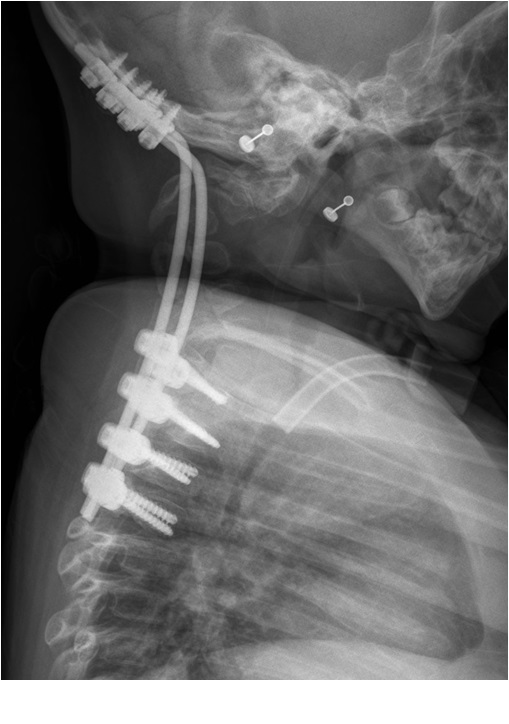

- Figura 5. Radiografias post. caída, muestra full out de tornillos occipitales

- Figura 7. Radiografías Post revisión AP y Lateral